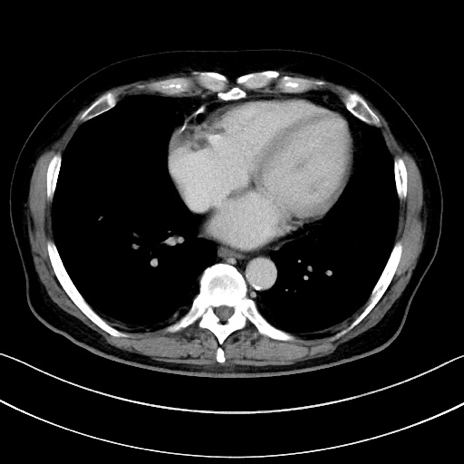

冠状断像